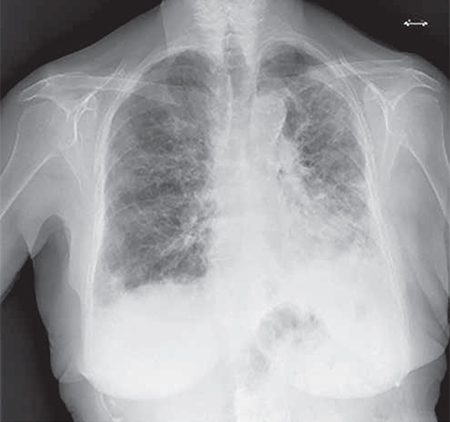

En las imágenes de rayos X de tórax, la EPI se manifiesta como una distribución irregular de opacidades que pueden variar en apariencia, incluyendo vidrio esmerilado, reticular, nodular, reticulonodular o quística. Estas opacidades representan áreas de inflamación e infiltración en el intersticio pulmonar, el espacio entre las células alveolares y los capilares pulmonares. Los patrones radiográficos típicos son indicativos de la afectación del tejido intersticial, y su presencia puede ayudar a diferenciar la EPI de otras enfermedades pulmonares.